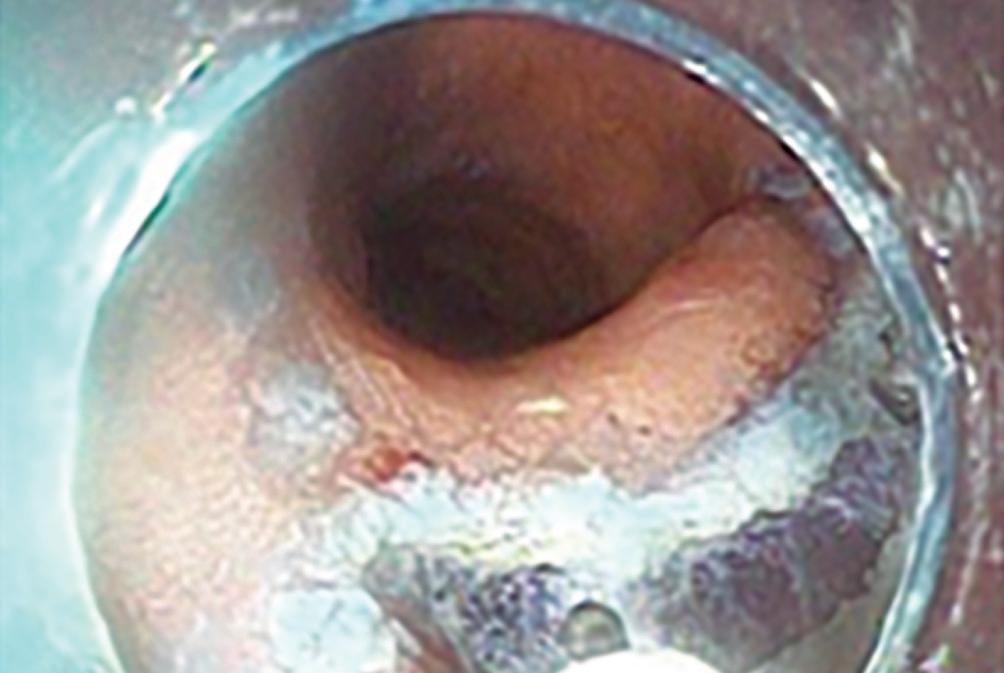

Si el tumor aumenta de tamaño con las deposiciones o los esfuerzos físicos, debemos considerar la presencia de un prolapso hemorroidal. Las hemorroides se clasifican según el grado de prolapso.5 Habitualmente, el paciente con prolapso hemorroidal no presenta dolor, aunque sí puede haber sangrado con las deposiciones. La proctorragia debe hacernos investigar la presencia de lesiones colónicas sincrónicas con videocolonoscopía. El tratamiento inicial es médico, con flebotónicos, pomadas locales, baños de asiento, fibras dietéticas e hidratación.6 En casos donde persisten los síntomas de prolapso o proctorragia, se pueden ofrecer tratamientos no resectivos como ligaduras elásticas, macro ligaduras elásticas o procedimientos láser para hemorroides. (Figura 4) En casos de hemorroides de gran tamaño, se indica la hemorroidectomías con técnicas como Milligan y Morgan o Ferguson.7

Figura 4. A) Hemorroides de grado 3 con prolapso reductible con maniobras manuales. Se evidencian dos paquetes hemorroidales internos con prolapso, de superficie mucosa roja y congestiva. El prolapso produce sensación de tumor anal, proctorragia y mucorrea. B) Se observa el resultado luego de la realización de una macroligadura hemorroidal